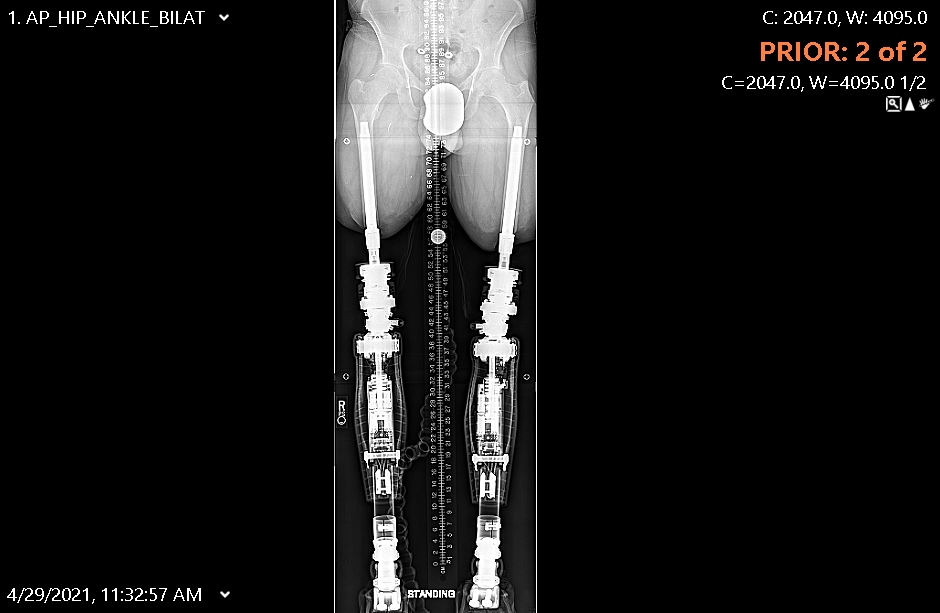

In April of 2019, after a rocket injury in the military, I came to the United States seeking treatment for bilateral transfemoral amputations. The first hospital I went to was in Texas where they helped me to use an above-the-knee prosthesis. Even though I worked with an amazing medical team and had intensive physical therapy for over five months, the treatment failed due to the limited soft tissue in my legs. This resulted in a very painful experience with these prosthetics. One of the doctors told me about osseointegration, a surgical procedure that aims to offer a better quality of lie and improved mobility for people who have had amputations. After hearing this, I contacted my embassy who recommended Hospital for Special Surgery without hesitation.

In December of 2020, the Saudi Arabia Embassy reached out to the International Center at HSS. This team acted quickly to secure an appointment with Dr. Rozbruch. Dr. Rozbruch recommended 1 stage, simultaneous bilateral femoral osseointegration as the traditional socket prosthetics were painful and do not fit given my limited soft tissue. In that same month, I underwent surgery and started my PT a few months later.